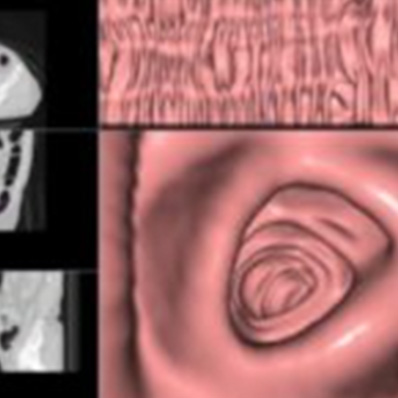

CTによる内視鏡検査

当院では、CT画像をデータ処理して行う仮想内視鏡検査も行っております。

カメラ(内視鏡)を飲む必要はなく、検査時間は約1分で、痛みもほぼありません。

仮想大腸内視鏡

大腸癌

大腸ポリープ